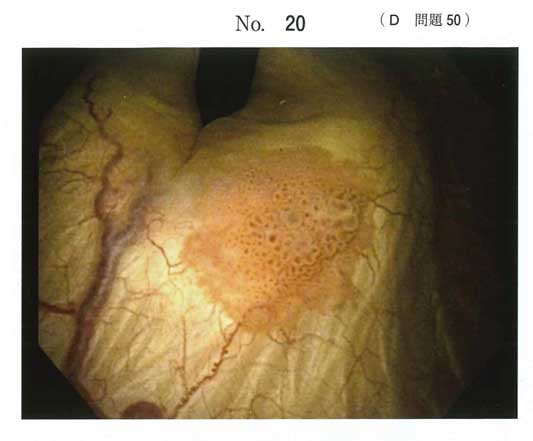

d)

まずはTUR-Btでしょう。そしてBCG膀胱注入を追加する。

膀胱腫瘍を見たら、まずTUR-Btなんですね。

病理で深達度や異形度を評価する

高リスクの非筋層浸潤性膀胱癌ならBCGで追加治療するんですかね。

全摘はTUR-Bt後の病理で筋層浸潤があればやるんですかね